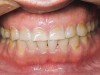

Figure 2   Asymmetric tooth wear in a bruxism triad patient as a result of friction from bruxing, poor salivary lubrication as a byproduct of medication, and roughened surfaces created as a result of erosive reflux.

Figure 2